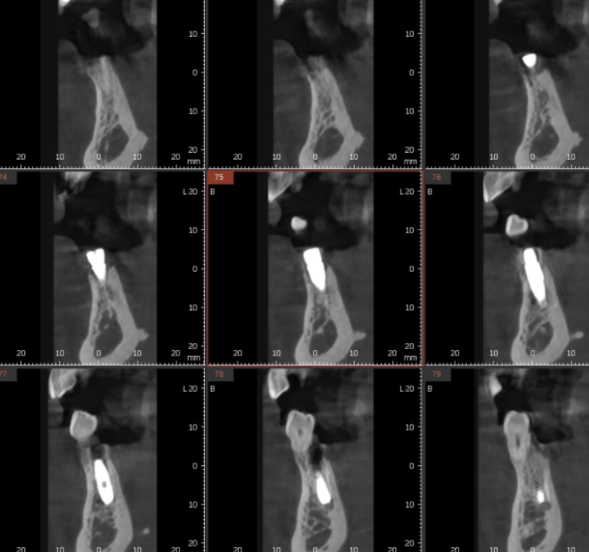

3d ct를 통해 분석

뼈가 충분한 곳에 명일동 임플란트를 심고

기계를 통해 뼈랑 얼마나 잘 붙었는지

확인하였을때

▼명일동 치과 하루 임플란트 결과▼

80 이상 수치가 나오면

내 뼈와 잘 붙은겁니다.

환자분도 81/80

두곳에서 수치를 재어보았을 때

80이상이 나와서 뽄을 떴습니다.

(수술 당일 측정)